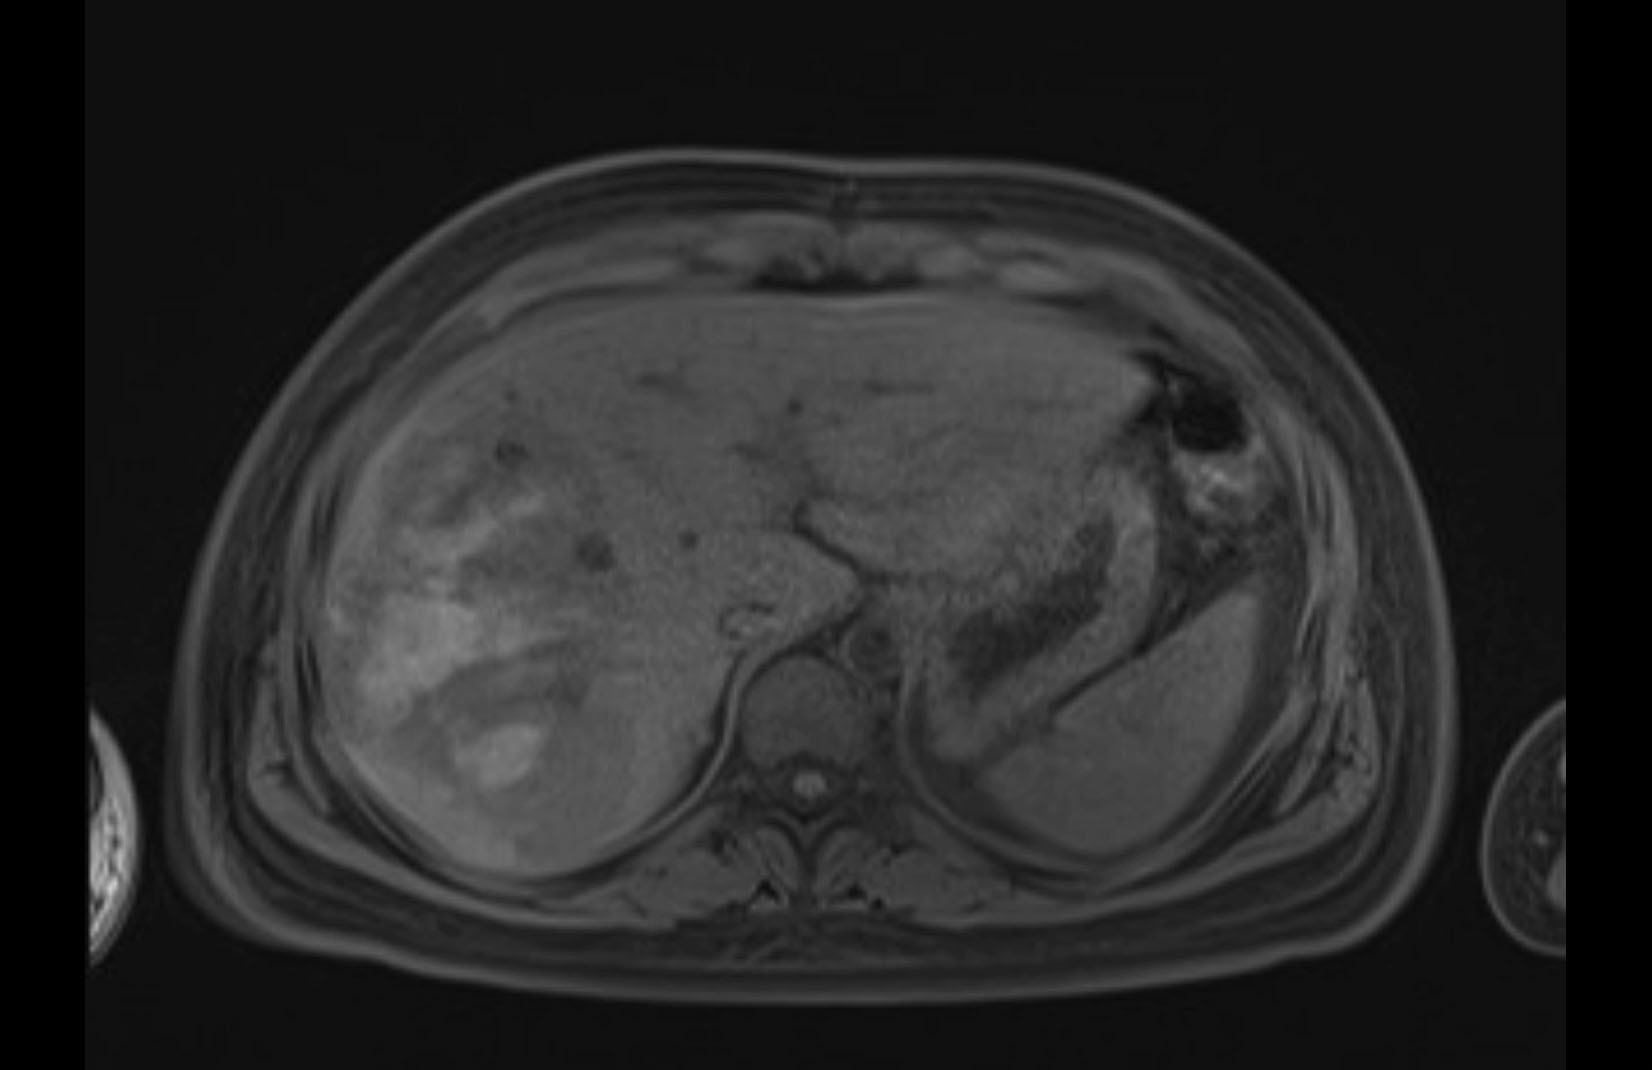

MRI T1

MRI T2